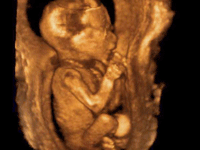

3D исследование показывает принципиально иную картину: изображение цветное, объемное, а внешность плода видна практически до мельчайших деталей. Частотой сканирования, интенсивностью и мощностью волн, такое исследование не отличается от двухмерного, но продолжительность УЗИ увеличивается втрое: с 15 минут до 45-50.

Существует также вариант 4D УЗИ, где четвертым измерением (помимо длины, высоты, глубины картинки) выступает время. Так, если трехмерному УЗИ свойственна статичность, то 4D отражает движения в реальном времени.

Оптимальный срок для 3D исследования — после 24-й недели беременности. Объясняется все просто: к этому периоду уже сформированы и достаточно хорошо видны наружные органы. Поэтому ряд дефектов (например, расщелину губы, неба) можно рассмотреть отчетливо.

Видео 3D УЗИ при беременности 24 недели. На этом сроке на 3D УЗИ уже четко видны ручки, ножки, голова, личико и даже волосики будущего малыша.